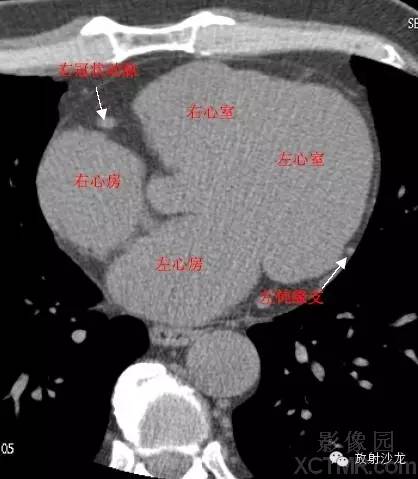

LA -Left Atrium左心房

RA -Right Atrium右心房

LV -Left Ventricle左心室

RV -Right Ventricle右心室

LMA -Left Main Artery冠状动脉左主干

LAD -Left Anterior Descending Artery左前降支

GCV–Great Cardiac Vein心大静脉